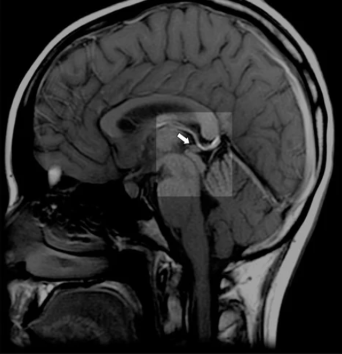

Here's what conventional medicine knows but rarely discusses: The pineal gland calcifies more than any other tissue in the human body. By middle age, many people's pineal glands contain calcium deposits visible on MRI scans, forming what researchers call "brain sand" or corpora araceacea.

normal pineal gland

calcification of the pineal gland